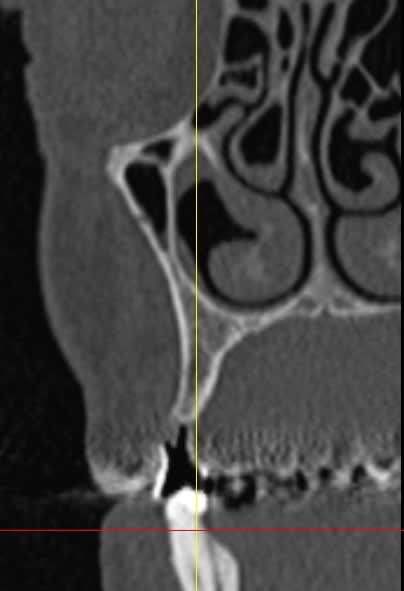

des avis?

non, le bas est fini, mais la chir du haut c'est pour bientôt, photos et vidéo si je peux, et que ça marche ou pas je montre tout, (nous intégrons de plus en plus la gestion des échecs dans nos présentations, ça plait aux inscrits car il y a quasiment toujours une solution)

Effectivement le secteur 3 est curieux radiologiquement mais il y a des raisons ... l'expansion à la mandibule, fut...sportive.

Pour l implant sur 14 il manque de l os en vestibulaire? Mise en place d os synthetique et membrane ou prelevement ramique?

Pour la 16 , une augmentation par abord lateral ou orthograde( desole je me souviens plus du nom de la technique).

l'expansion, ou manipulation osseuse, c'est utiliser l'os existant, en doublant ou triplant son volume...

la radio sert à vérifier la position de la lame 15, par rapport à la racine et au sinus, mais je ne suis pas sur que tu comprennes, que le bistouri est dans l'os, c'est l'instrument le plus fin et le moins traumatisant pour fendre l'os (je le préfère au piezzo et même au disque diamanté).

Bonjour, pour la 16 ,tu peux faire une ostéotomie de SUmmers, tu as plus de 4 mm d'os .

Un implant de 10 mm devrait suffir.

Pour la 12 ou 13 utilise les expanseurs, prévoit un 3,6